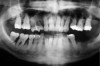

The clinician also must consider the status of the adjacent teeth. Figure 6 shows teeth Nos. 29 and 31 prepared for a fixed bridge. Factors to be considered in this example were the short root of tooth No. 29 with a distal biologic width violation and a short root trunk on tooth No. 31 (which leads to furcation involvement with a small amount of facial or lingual bone loss). This patient also had periodontal disease, which further decreased the long-term prognosis of the fixed bridge option. No prospective studies directly compare the longevity of the two options: a three-unit fixed bridge vs an implant.37 Other factors that complicate comparisons of an implant vs a fixed three-unit bridge are the variability of fixed bridges as well as the variability of the implants (amount of bone, implant length, etc). For example, endodontically treated abutment teeth do not last as long as nonendodontically treated abutment teeth.38 Restorations on teeth with endodontic posts and a minimal length of ferrule do not persist as long as those on teeth without a post and at least a 2-mm ferrule.39

Figure 6   Tooth No. 29 with the temporary build-up close to the osseous crest. Tooth No. 29 has a short post, and tooth No. 31 has a very short root trunk.

Figure 6